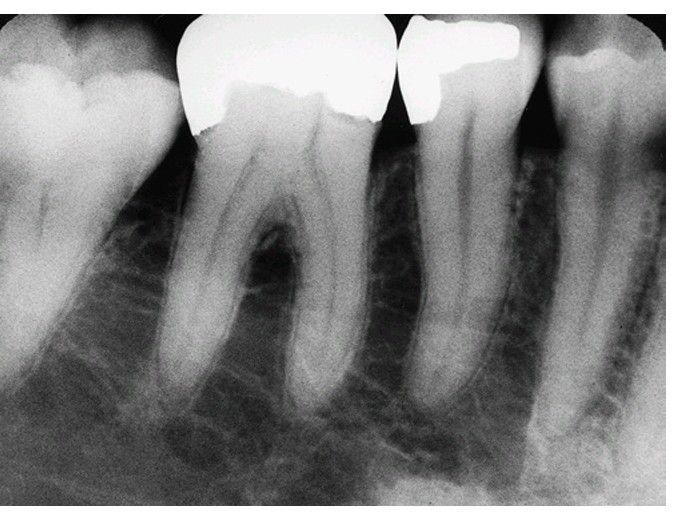

Dislodgment of adjacent restoration

Mandibular first molar. If the first molar is to be removed, the surgeon must take care not to fracture amalgam in the second premolar with elevators or forceps.